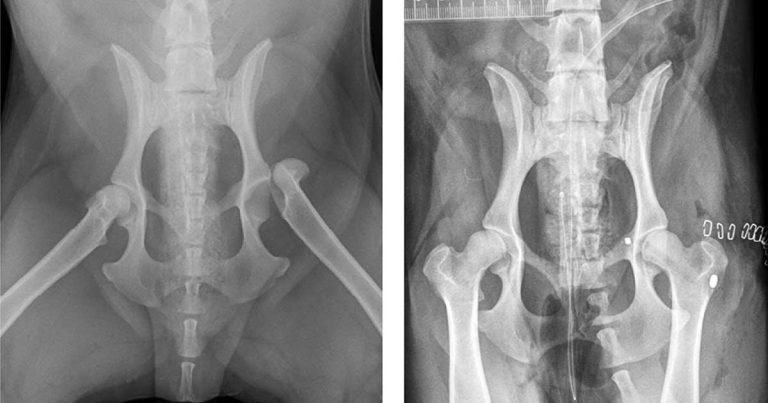

Figure 1. Preoperative and postoperative radiographs of the ventrodorsal hips showing fixation of a left coxofemoral luxation using a “toggle” procedure.

In this case, the haemoabdomen was stable and the rectal bleeding was confirmed as colitis, resolving over 24 hours, along with the ventricular premature complexes. Further stabilisation and intensive monitoring was continued for five days until it was safe enough for surgical fixation of the orthopaedic injuries (Figures 1 and 2).